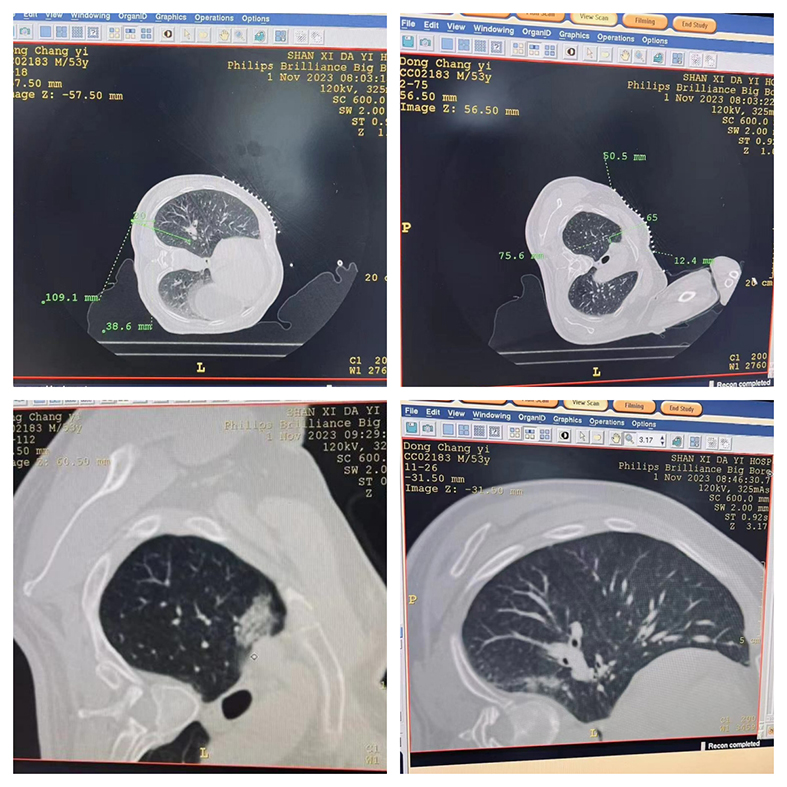

▲患者入院检查图